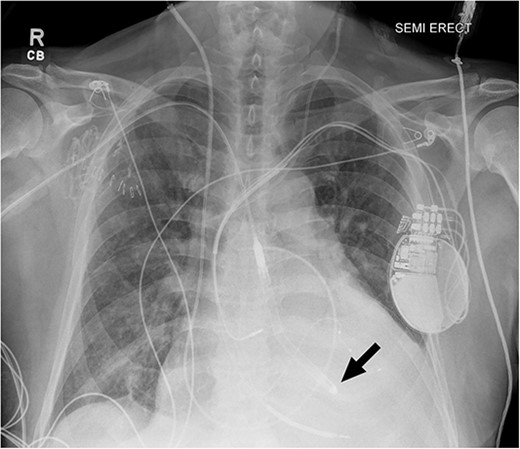

Despite escalating inotropic support and diuresis, the patient deteriorated—a femoral IABP was inserted on hospital day 3. Despite support with IABP, he remained with evidence of end-organ dysfunction and refractory cardiogenic shock. After 9 days of support, his MCS platform was upgraded to an axillary Impella 5.5® to provide better systemic support with active unloading of the left ventricle (Fig. 1). Hemodynamic parameters improved (PAP, 35/15 mmHg; PCWP, 13 mmHg; CI, 3.5 L/min/m [2]), and creatinine decreased to baseline. The Medical Review Board consensus was bridge to heart transplantation as UNOS Status 2.

Chest radiograph after Impella 5.5® placement demonstrating adequate placement across the aortic valve into the left ventricle. The arrow indicates the tip of the Impella positioned in the left ventricle.